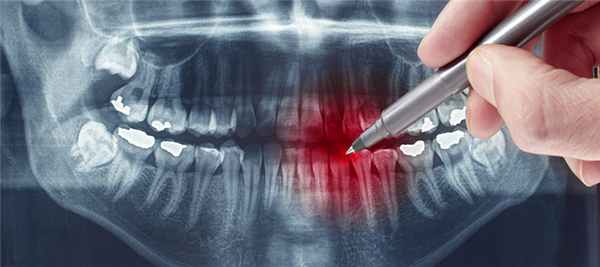

а) Терминология:

• Синонимы:

о Гипоплазия Тернера, зубы Тернера

• Определение:

о Дефект эмали постоянных зубов, обусловленный одонтогенным воспалением или травмой временного зуба-предшественника

б) Визуализация:

• Лучший диагностический критерий:

о Отсутствие эмали и неровная поверхность дентина изолированного зуба

• Локализация:

о Наиболее часто премоляры, реже-любой другой зуб

о Постоянные моляры никогда не поражаются (нет предшественников)

• Задние зубы:

о Деформация коронки с отсутствием эмали

о Неровная поверхность дентина

• Передние зубы:

о Горизонтальные гипопластические тяжи низкой плотности поперек коронки зуба

о Часто имеется связь с травмой

• Лучший метод визуализации:

о Периапикальная рентгенография

о Ищите расширение верхушечного пространства периодонтальной связки, рарефицирующий остеит или конденсирующий остеит как следствие восприимчивости зубов к кариесу с последующим возникновением патологии пульпы

(Слева) На периапикальной рентгенограмме у пациента с дисплазией Тернера определяется утрата тканей коронки первого премоляра нижней челюсти слева. Расширение пульпового канала может быть обусловлено внутренней резорбцией или удалением избыточного количества тканей во время вмешательства на канале.

(Справа) На периапикальной рентгенограмме у пациента с дисплазией Тернера визуализируется импактный второй премоляр нижней челюсти. Обратите внимание на неровный край эмали и дентина коронки.

в) Дифференциальная диагностика дисплазии Тернера:

• Несовершенный амелогенез:

о Генетическая аномалия

о Поражение всех или почти всех постоянных и временных зубов

о Квадратные коронки, истончение или отсутствие эмали

о Открытые контакты между зубами: картина штакетника

• Гипоплазия эмали в результате внешних влияний:

о Множественное поражение зубов

о Обычно имеется привязка к определенному событию: вдыханию наркотиков, дефициту питания, лучевой терапии

о Поражение коронок при внешнем воздействии в определенное время развития зуба

• Подготовленная коронка:

о Ятрогенное воздействие

о Зуб может быть уже подготовлен под протезирование коронки или реставрацию

о Возможно, что реставрационный материал или протез коронки выпал или никогда не был установлен

о Изучение анамнеза должно прояснить этот вопрос

г) Клинические особенности:

• Наиболее типичные клинические проявления:

о Дефекты зуба варьируют от фокальных участков белого, желтого, коричневого цвета до распространенной гипоплазии всей коронки

• Течение:

о Воспалительное или травматическое поражение временных зубов

о Воздействие передается на формирующиеся постоянные зубы

о Поражение формирующейся эмали и дентина о Тяжесть зависит от силы воздействия и стадии развития постоянных зубов

о Возможно нарушение формирования матрикса эмали или его обызвествления и, как следствие, местный гипопластический или гипоминерализационный дефект

о Более тяжелое воздействие может приводить к образованию вдавлений на коронках или выраженной деформации

• Лечение: полностью прорезавшийся зуб может быть восстановлен:

о Небольшой дефект: реставрация композитными материалами

о Крупный дефект: протезирование коронки, вмешательство на корневых каналах, установка коронки на штифте при периапикальной патологии

д) Диагностическая памятка:

• Исследуйте другие зубы на предмет дефектов

• Изучите анамнез на предмет вероятных причинных событий